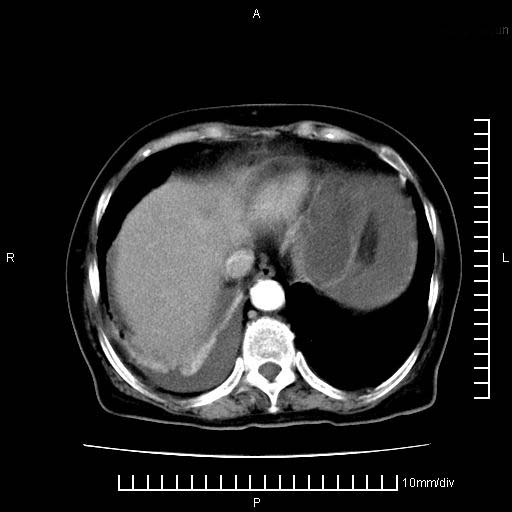

标题: CT28280:腹部增强:女性,80岁

上腹疼痛月余,外院核磁诊断胰腺癌。现临床示右下腹可明显触及包块,可片子上怎么没有看到?

1.胰腺颈体部癌。

2。腹腔积液。

3。右胸腔积液,伴右肺下叶部分萎陷。

4。右肾盂囊肿。

1。胰腺ca伴腹膜腔转移

2。肝左叶低密度灶,考虑转移可能

胰腺结构模糊,胰尾部见囊性包块,周围脂肪密度增高,左肾前筋膜增厚,胸水、腹水。不符合胰腺ca伴腹膜腔转移。考虑胰腺炎伴假性囊肿形成、胸腹腔积液。

右肾盂囊肿。

1)考虑胰腺癌并胰腺假性囊肿形成。2)肝内低密度灶,不排除转移。3)右肾盂积水。4)腹水。5)右侧胸腔积液并右肺下叶部分膨胀不全。